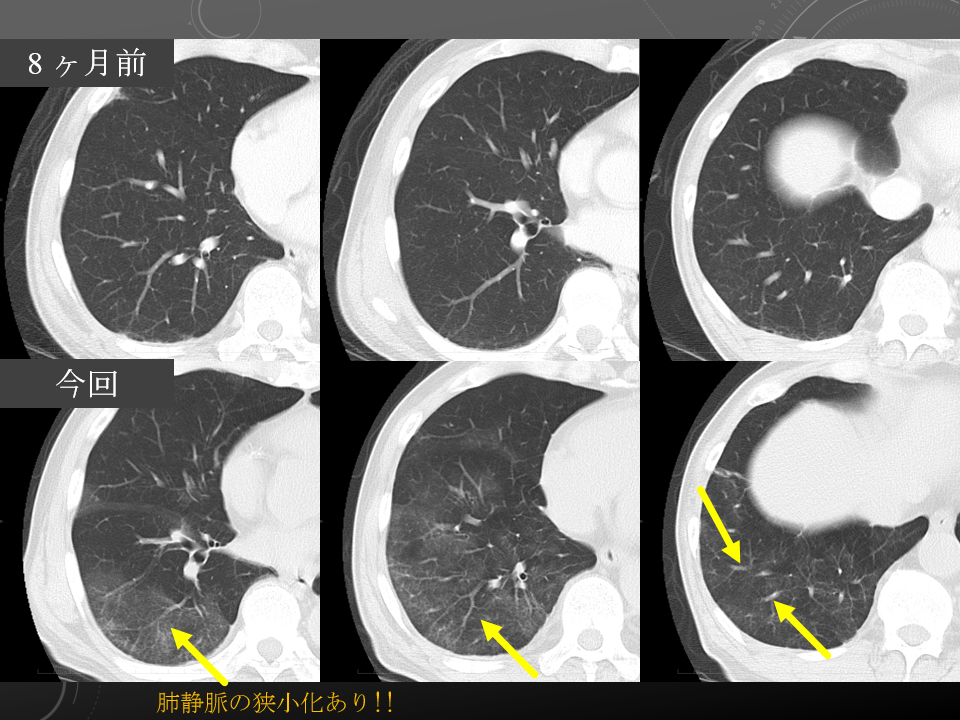

肺静脈の狭小化あり